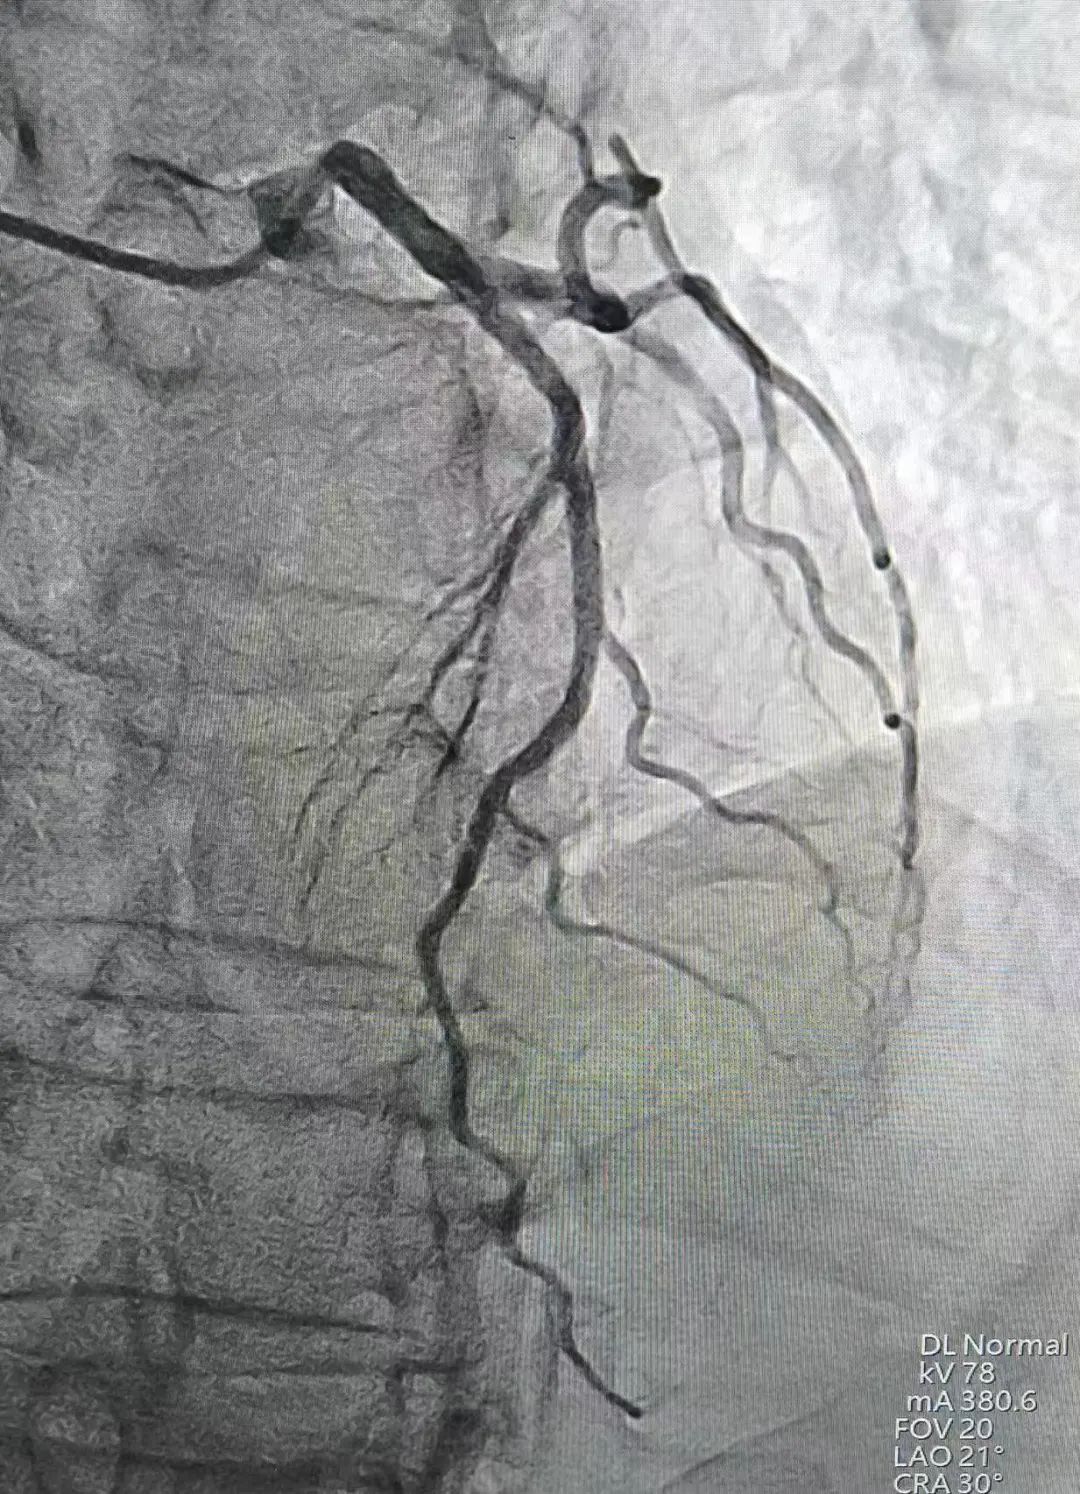

全脑血管造影术+心血管造影术

1、损伤小。通过一次穿刺即可同时完成冠状动脉、全脑血管的检查,局部损伤小,出血少,减少患者痛苦。